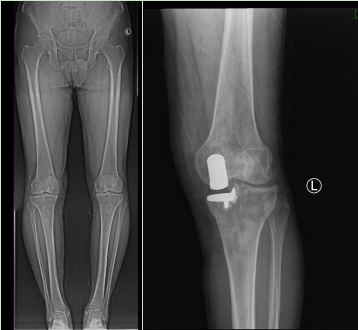

姚俊娜主任认真为其做了体格检查,结合病史及相关辅助检查,诊断为左膝内侧骨性关节炎。姚俊娜主任带领科室团队认真研讨手术方案,为患者制定了详尽的术前计划,并成功实施了左膝内侧单髁置换术。术后医生护士们耐心指导马先生下地行走锻炼,为其讲解骨关节病知识及回家康复注意事项。出院后冯伟医生还多次打电话耐心询问其身体恢复情况,让马先生一家人倍感温暖。马先生目前已能够正常活动,生活质量显著提高。